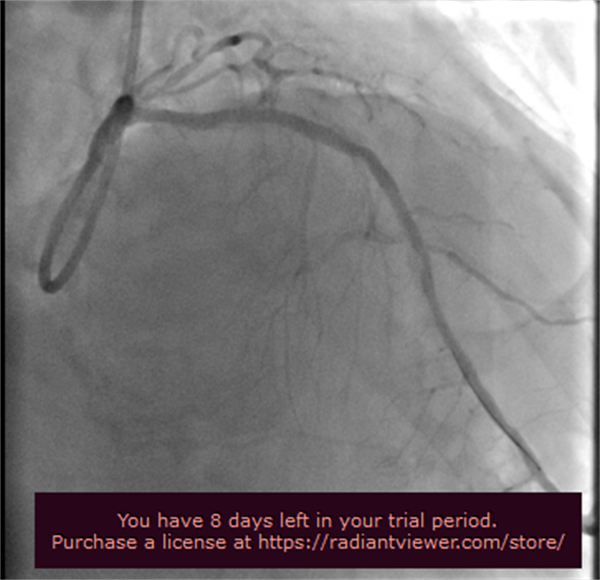

随后在张海涛教授的指导下,李钢、王志勇、鞠静等专家团队紧密配合,采用1.5mm的旋磨头,每次旋磨持续15~30秒,间隔30秒~2分钟,以保证充分清除碎屑。如此反复旋磨,终于打通“隧道”,并在前降支近-中段植入2枚支架,手术顺利完成。

冠状动脉旋磨术的开展,填补了我院心血管介入这一技术领域的空白,拓宽了冠脉介入适应征,提高了复杂冠脉介入治疗的成功率,为冠状动脉严重钙化患者创造了血管重建的机会,标志着北京燕化医院冠脉介入治疗水平又上一个新台阶。